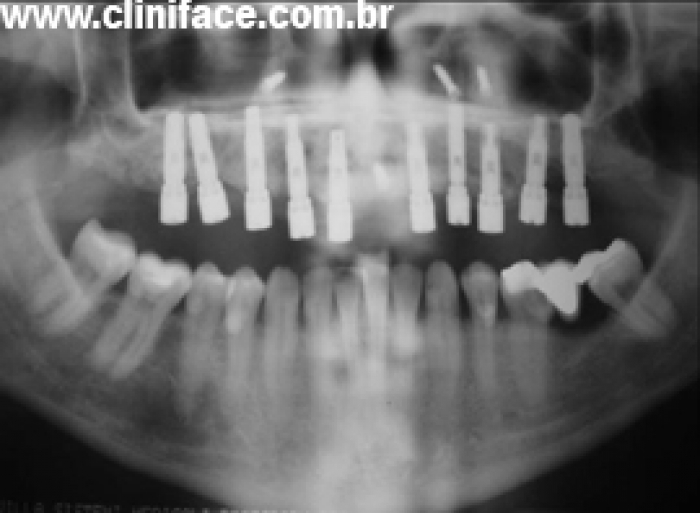

Raio X final